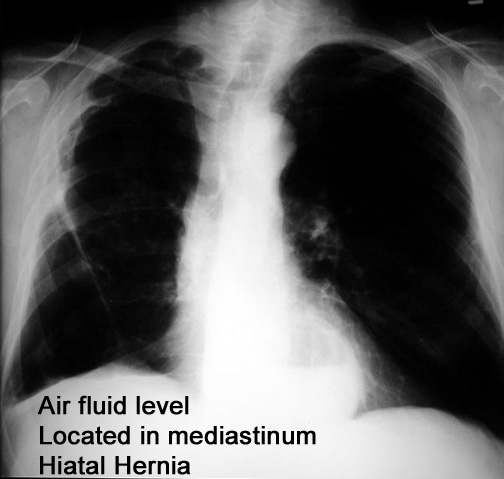

What is the differential for air fluid levels in the mediastinum?

Case 13 Labeled Image What is the differential for air fluid levels over the cardiac density?